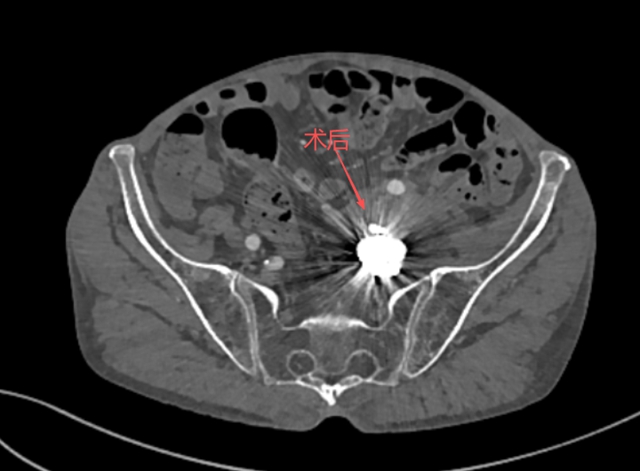

出院前,张大爷再次接受了血管造影检查。结果显示左侧髂内动脉瘤栓塞彻底,覆膜支架位置理想,血流畅通无阻。这个差点夺走他生命的血管危机,被成功化解。

术后